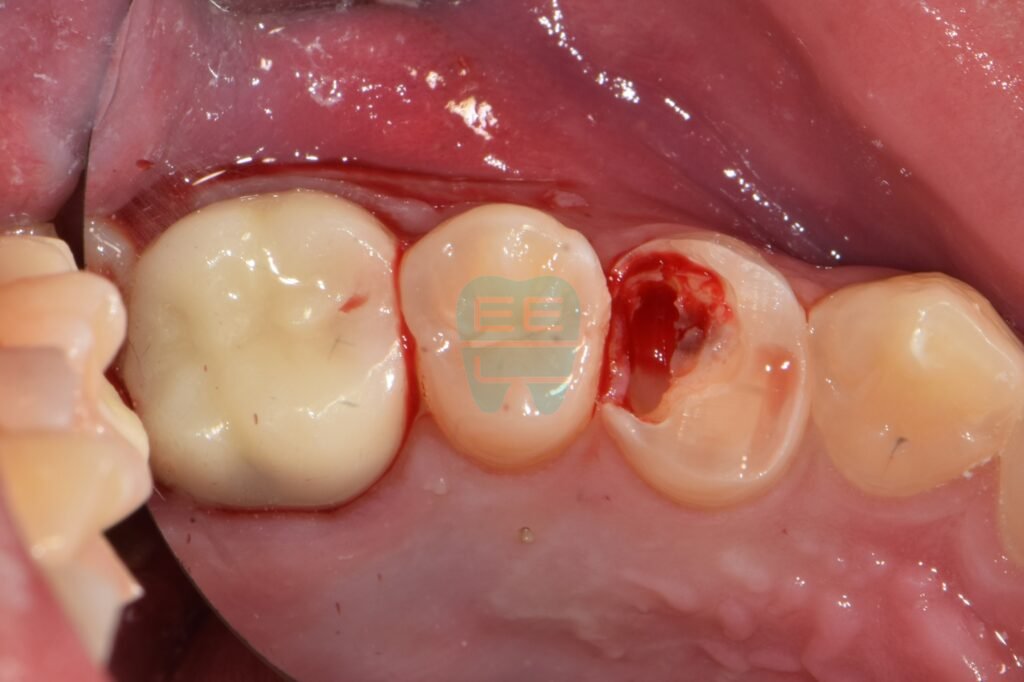

1. 치료 전 상태 (Before): 잇몸이 점령한 치아

처음 오셨을 때의 모습입니다. 충치가 심하게 진행되어 치아 머리 부분의 대부분이 사라졌고, 그 빈 공간을 부어오른 잇몸 살이 가득 채우고 있었습니다.

잇몸이 치아 내부까지 침범해 있어, 건드리면 피가 나고 어디가 치아이고 어디가 잇몸인지 구분하기 힘든 상태였습니다.